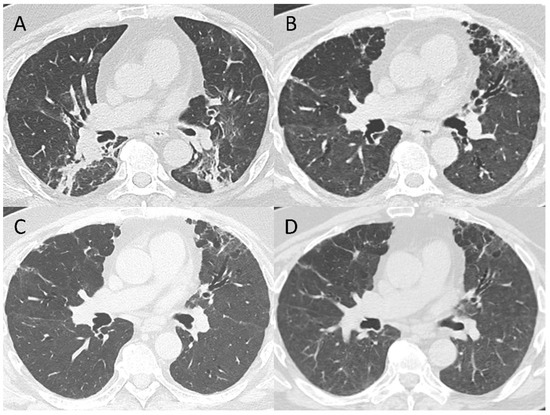

3.2. 5–7-Month Follow-Up CT Scan

3.4. Pattern Evolution